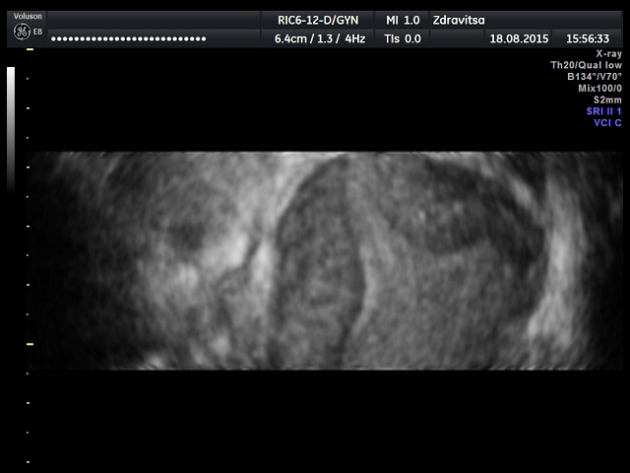

Предлагаю вашему вниманию мини видео пример. Может и простой пример, но для повторения - мать учения. Что с маткой, коллеги?

Двурогая матка.

Полное разделение.

Случайно было обнаружено при обычном УЗИ осмотре у девушки подростка.Хотя вопрос стоял и о седловидной матке

Форма седловидной,но полное разделение эндометрия.